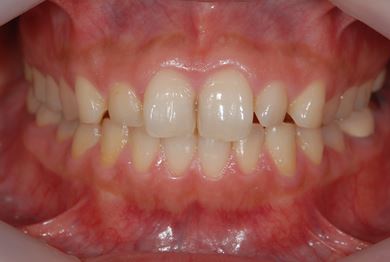

インプラント治療+セラミック治療+歯肉歯槽骨整形

| 性別/年齢 | 女性 / 38歳 | ||||||||||||||||||||||||||||||||

| 主訴 | 右下奥の欠損のため、インプラントを希望。また、左に物が挟まりやすいための治療も希望。 | ||||||||||||||||||||||||||||||||

| 治療内容 | インプラント1本、ジルコニアフレームオールセラミッククラウン2本(ジルコニアセラミック用土台1本)、歯肉歯槽骨整形 | ||||||||||||||||||||||||||||||||

| 総治療費 | 713,580円 | ||||||||||||||||||||||||||||||||

| 治療期間 | 10ヶ月 |